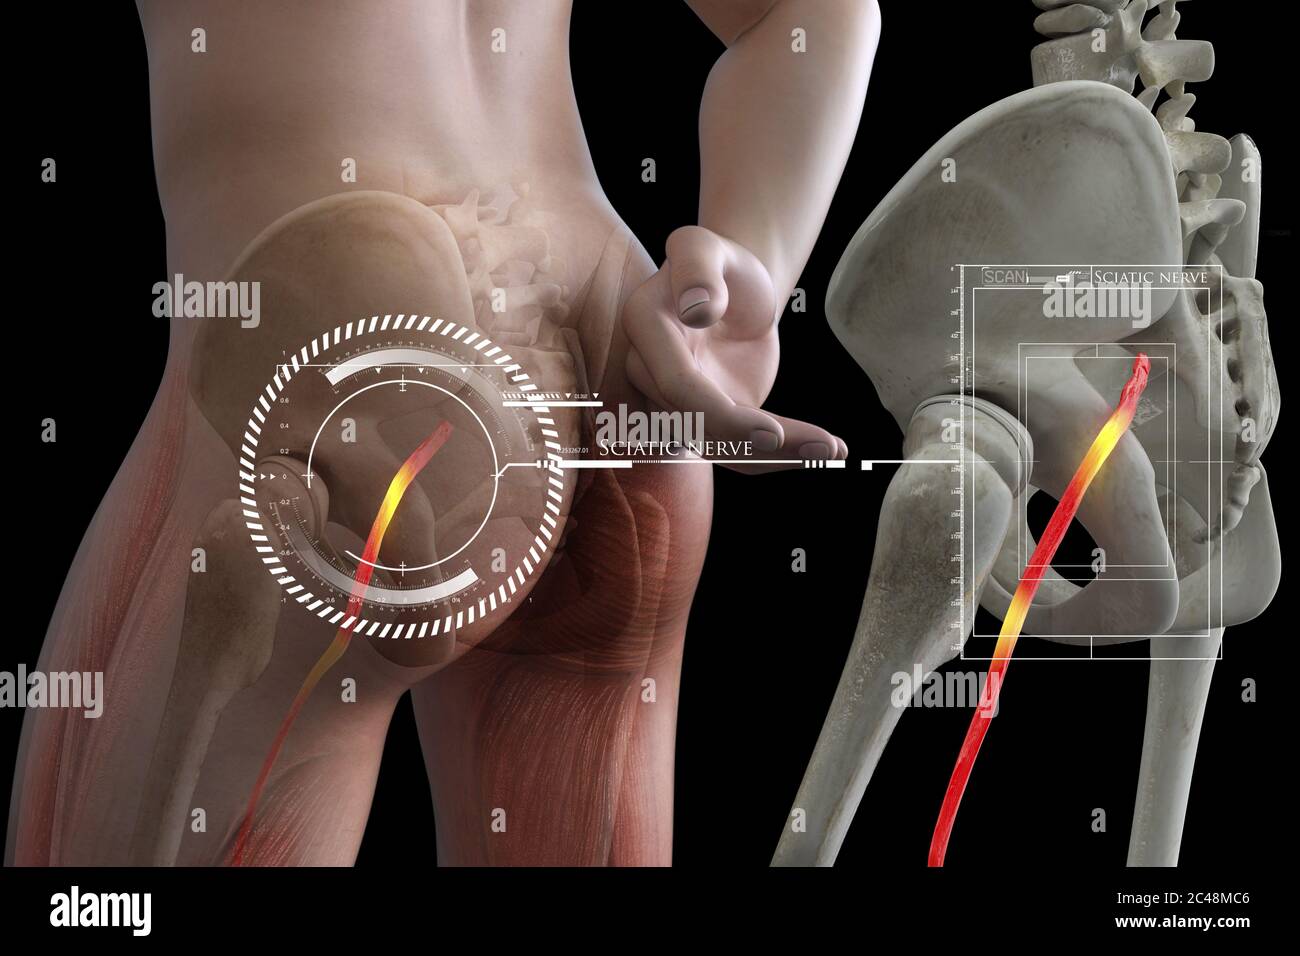

Nerf sciatique humain pincé, vision anatomique. illustration 3d. Banque D'Imageshttps://www.alamyimages.fr/image-license-details/?v=1https://www.alamyimages.fr/nerf-sciatique-humain-pince-vision-anatomique-illustration-3d-image364068055.html

Nerf sciatique humain pincé, vision anatomique. illustration 3d. Banque D'Imageshttps://www.alamyimages.fr/image-license-details/?v=1https://www.alamyimages.fr/nerf-sciatique-humain-pince-vision-anatomique-illustration-3d-image364068055.htmlRF2C48MEF–Nerf sciatique humain pincé, vision anatomique. illustration 3d.

Nerf sciatique humain pincé, vision anatomique. illustration 3d. Banque D'Imageshttps://www.alamyimages.fr/image-license-details/?v=1https://www.alamyimages.fr/nerf-sciatique-humain-pince-vision-anatomique-illustration-3d-image364067992.html

Nerf sciatique humain pincé, vision anatomique. illustration 3d. Banque D'Imageshttps://www.alamyimages.fr/image-license-details/?v=1https://www.alamyimages.fr/nerf-sciatique-humain-pince-vision-anatomique-illustration-3d-image364067992.htmlRF2C48MC8–Nerf sciatique humain pincé, vision anatomique. illustration 3d.